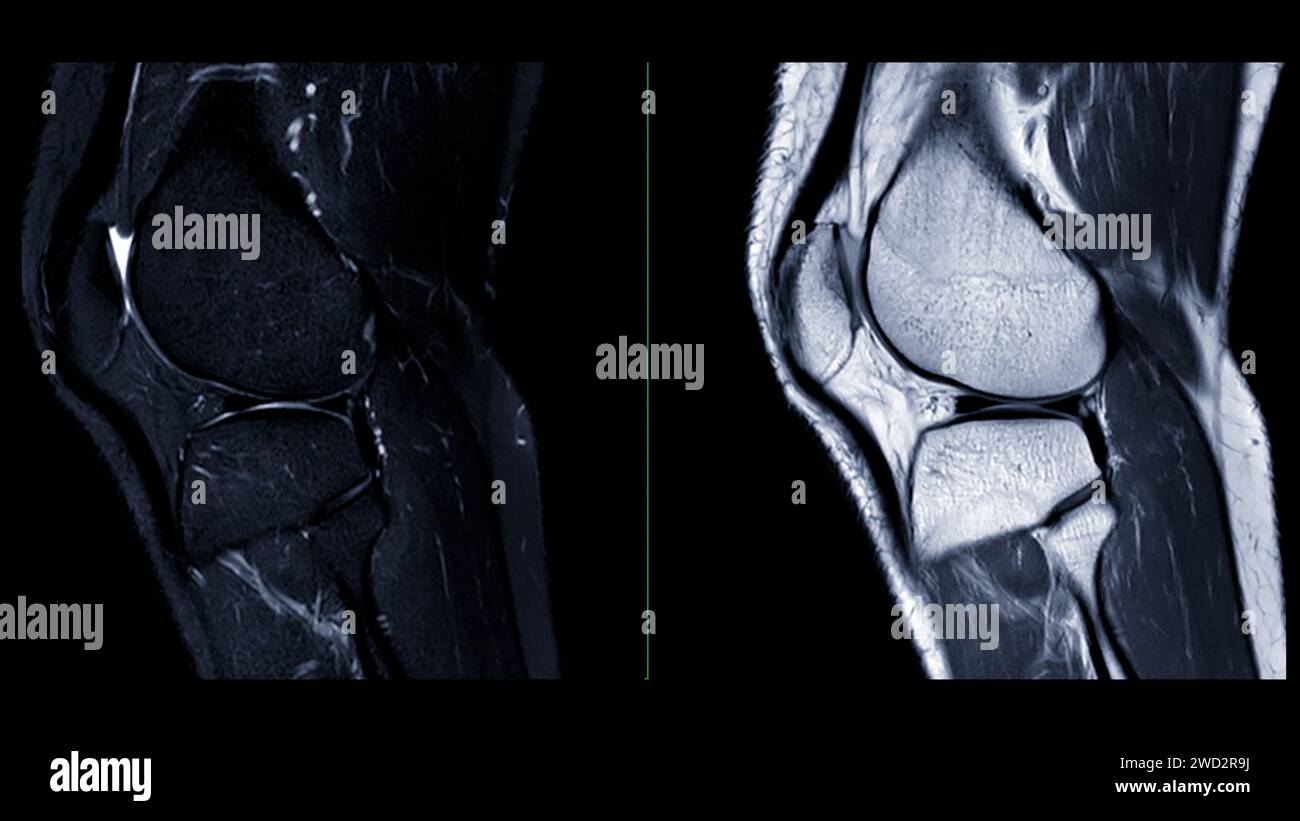

MRI Scan Knee Melbourne Melbourne Radiology Clinic

From www.melbourneradiology.com.au

resonance imaging or MRI of knee joint. This diagnostic Knee Cartilage Issues Cartilage damage can affect your knee in different ways. People may experience some or. If you have cartilage loss in your knee, it's important to follow healthy practices like losing weight, exercising, and seeing a healthcare provider or physical therapist. You may also experience a feeling of instability and weakness. What are the symptoms of osteoarthritis of the knee? A. Knee Cartilage Issues.